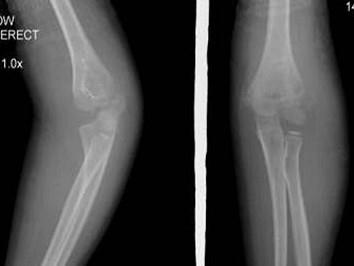

问题 6岁女性患者,因外伤后致左肘关节肿痛,活动受限,外踝局部压痛明显X线摄片如图,最合适的诊断是 ( )

选项 A、左肱骨小头骨骺IV度分离 B、以上都不正确 C、左肱骨小头骨骺II度分离 D、左肱骨小头骨骺III度分离 E、左肱骨小头骨骺I度分离

答案 C